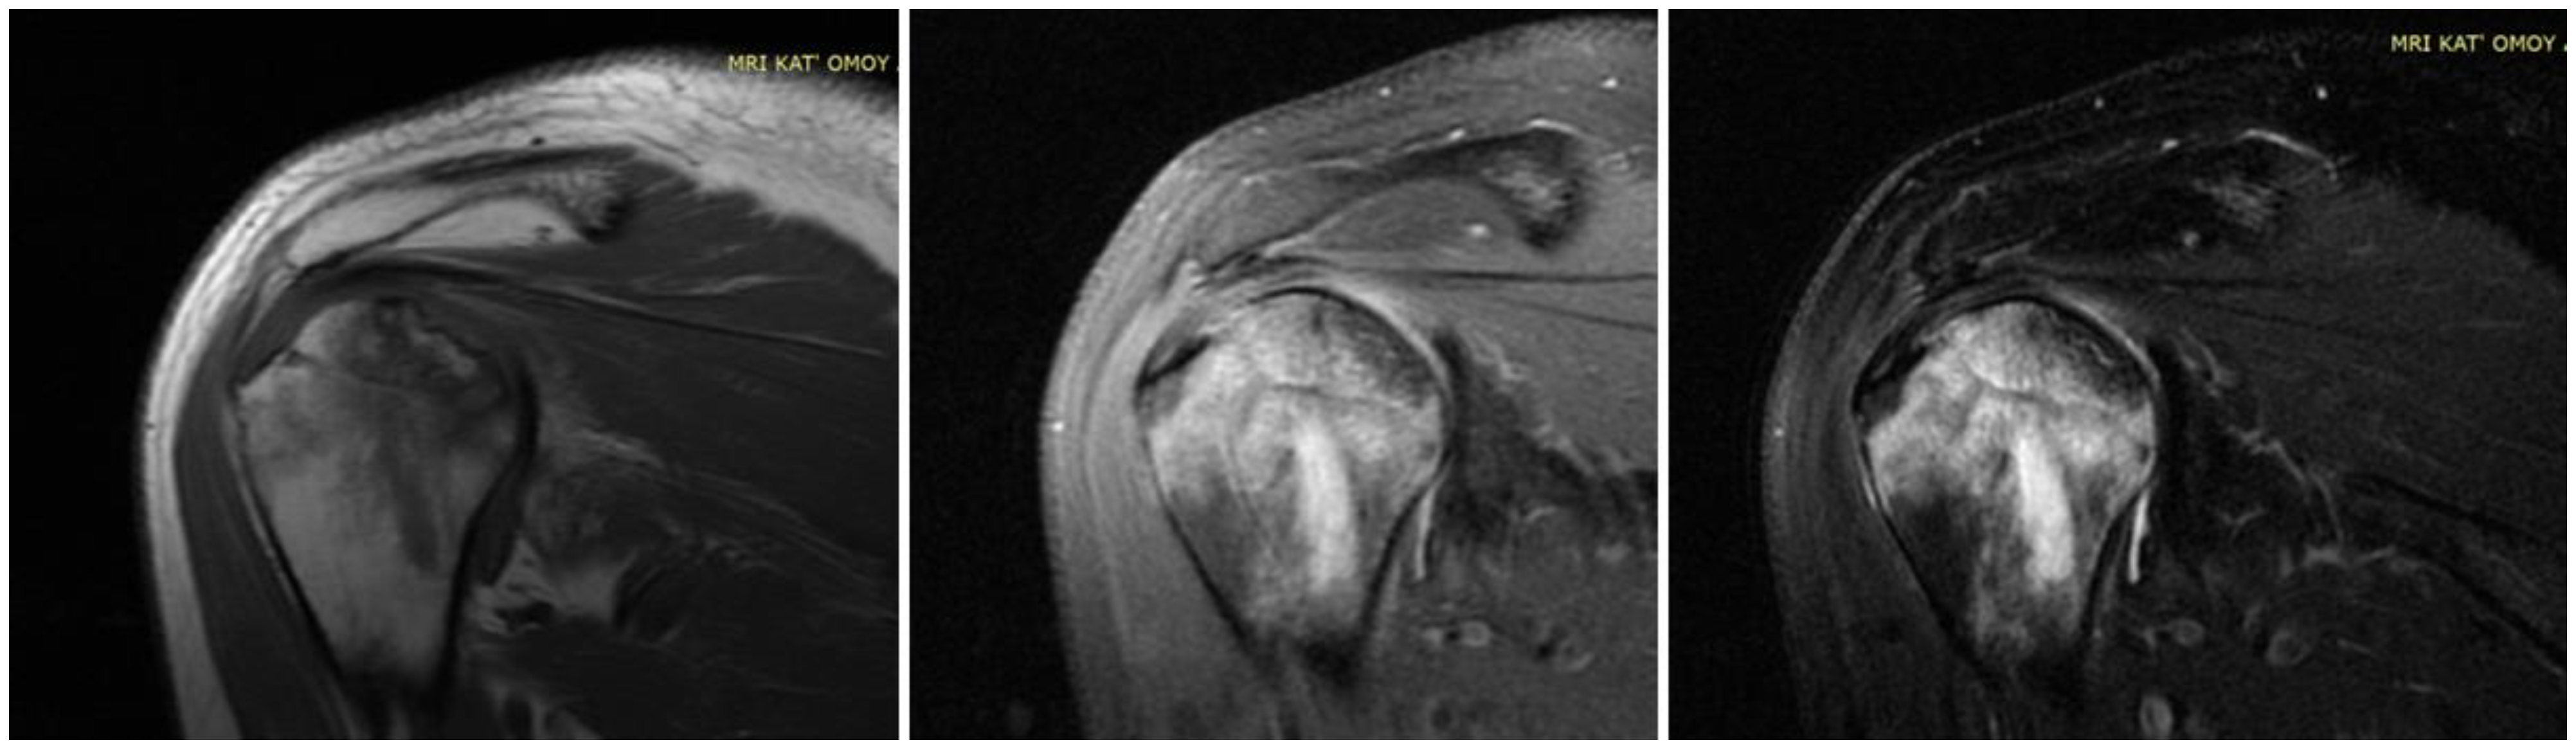

| 14. Kashkosh et al. (2022) [15] | Case report | 1 M | 40 | Second dose of the Pfizer COVID-19 vaccine | AVN of the humeral head | 2 | Analgesics Activity modification IA hydrodilatation inj | Improved ROM Severe shoulder pain Surgical intervention |